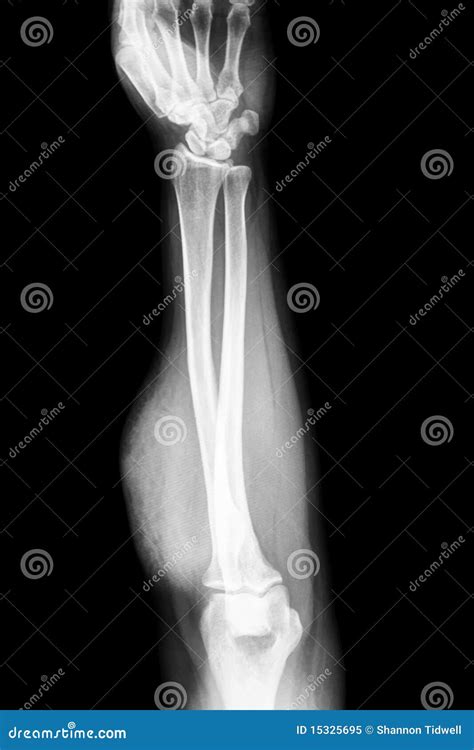

A forearm X-ray is one of the most common diagnostic imaging procedures performed in emergency departments, urgent care centers, and orthopedic clinics. Whether you have suffered a sudden fall, a sports-related injury, or are experiencing unexplained chronic pain, this imaging tool provides doctors with a vital, non-invasive look beneath the skin. By utilizing small amounts of electromagnetic radiation to create images of the bones in the forearm—specifically the radius and the ulna—medical professionals can accurately diagnose fractures, dislocations, and various other structural abnormalities. Understanding the procedure, why it is requested, and what the results mean can help demystify the process and prepare you for your visit to the radiology department.

Understanding the Anatomy of the Forearm

To interpret a forearm X-ray, it helps to understand the anatomy involved. The forearm consists of two long bones that work together to allow for flexibility and rotation:

The Radius: Located on the side of the thumb, the radius is the bone that primarily allows the forearm to rotate, enabling you to turn your palm up or down.

The Ulna: Located on the side of the pinky finger, the ulna is larger at the elbow and helps form the hinge joint necessary for bending the arm.

Anteroposterior (AP) View The arm is flat on the table, palm facing up, providing a front-to-back view of the radius and ulna.